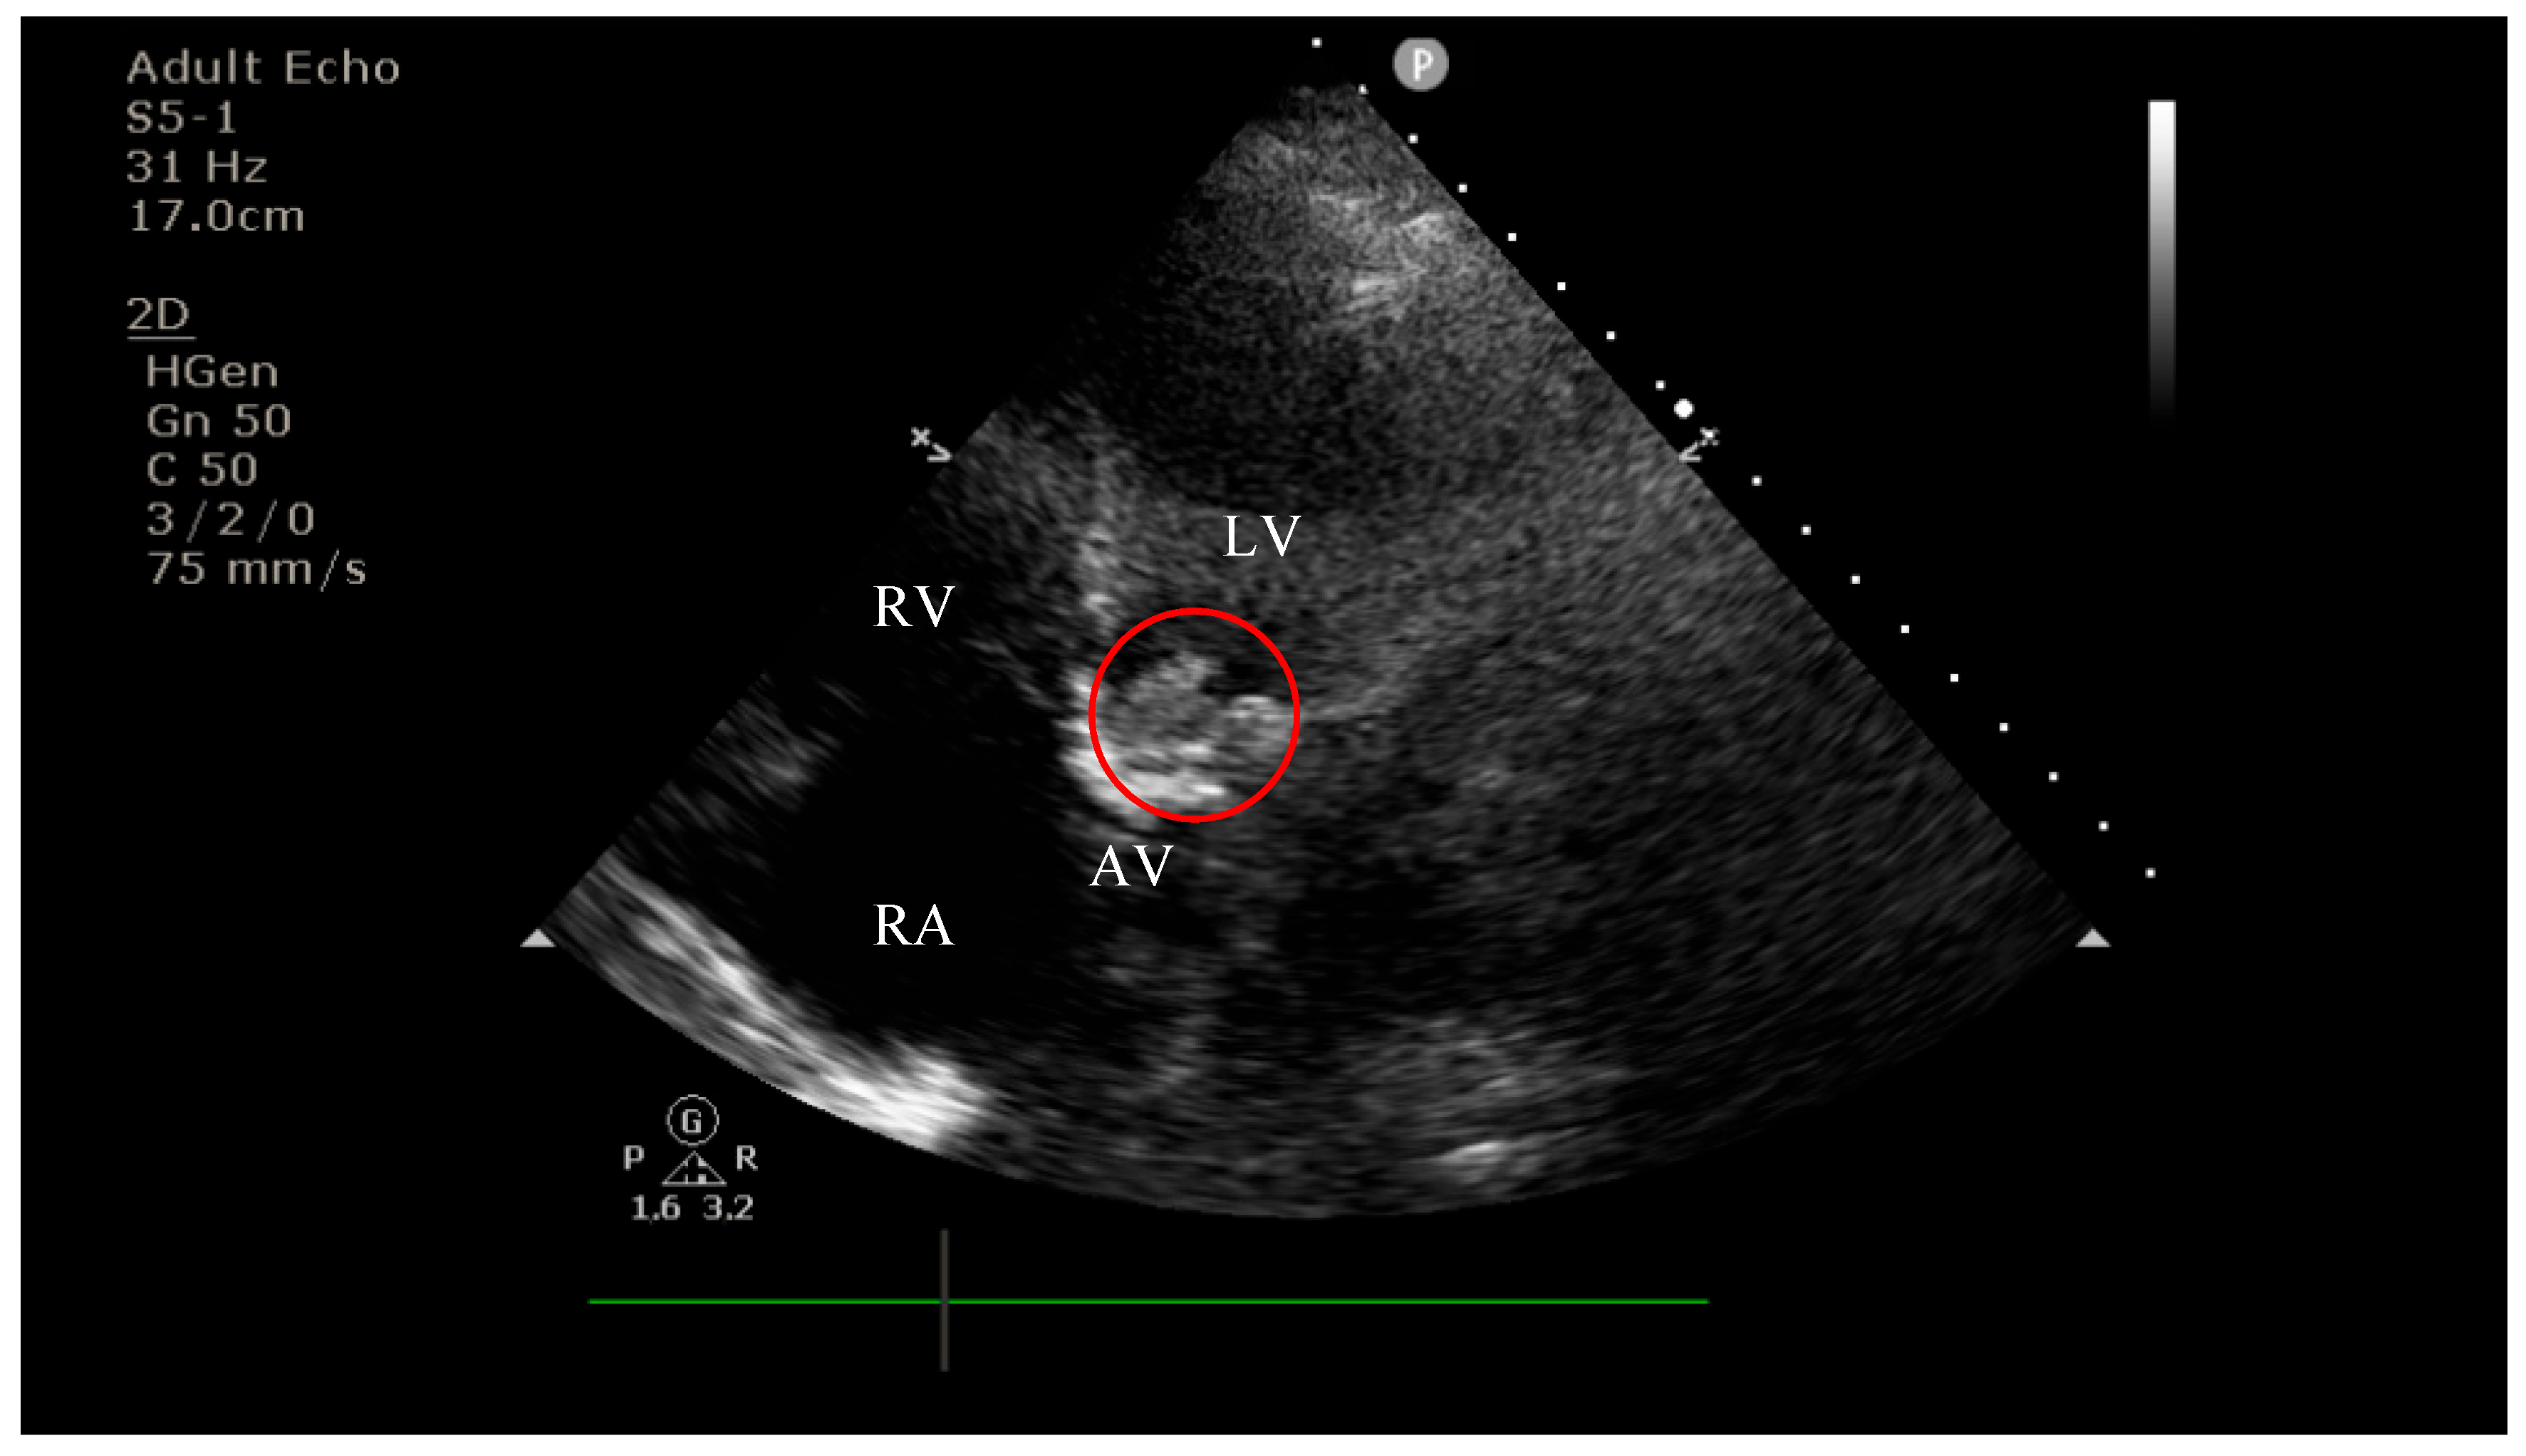

4.2. Diagnostic Findings: Mitral Valve Dysfunction and Embolic Phenomena

4.3. Coronary Complications and Diagnostic Dilemma